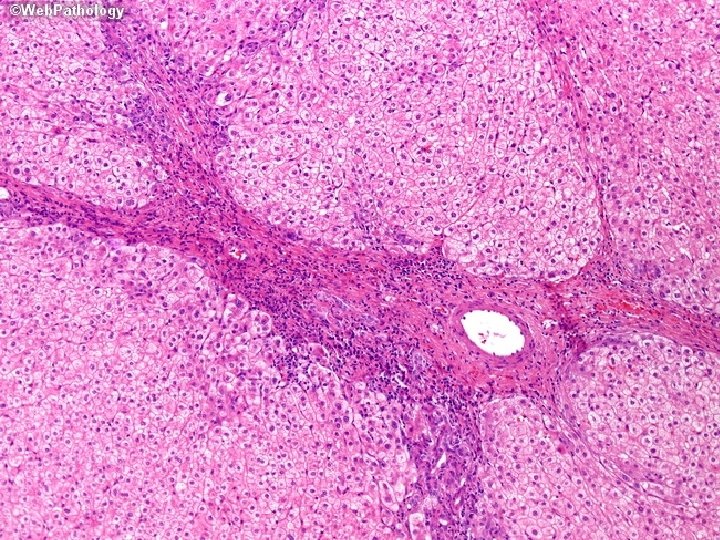

Focal Nodular Hyperplasia: v. Localized, well-demarcated, poorly encapsulated. v. Not a true neoplasm. v. No risk for malignancy. v. Nodules consist of: v. Hyperplasic hepatocyte with central stellate shap fibrous scar. (Star shape) Cause: (Suggestion) v. A response to abnormal blood flow Alternating areas of parenchymal regeneration & atrophy. v. Most common in women in reproductive age, growing in response to estrogens. (Female sex H. ) (Including those found in contraceptive pills).

Histologic examination: v. Sheets & cords of cells. v. Resemble normal hepatocytes. v. Or have minimal variation in cell & nuclear size. v. Portal tracts are absent. (Loss of normal architecture). v. Prominent arterial vessels & draining veins.

Histologic examination: 1 - Well differentiated lesions: Hepatocytes arranged in cords, trabeculae or glandular patterns with globules of bile found within the cytoplasm of cells.

Well-differentiated hepatocellular carcinoma: Distortions of normal structures: Liver cell plates are markedly widened & frequent pseudoacinar structures (arrows)—abnormal bile canaliculi contain bile.